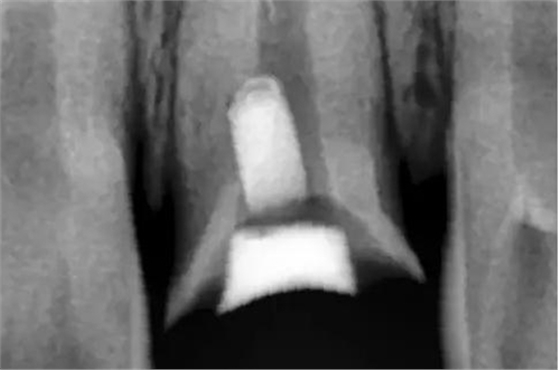

用MTA修補術后觀

術后X片